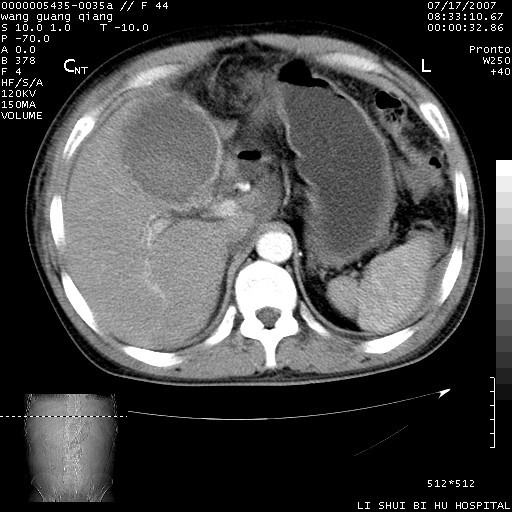

以下是引用dyqct在2007-7-18 10:46:00的发言:[br]胆囊明显增大,壁增厚,明显强化;后下方见大片高密度区,ct值68hu,无强化,周围见多数条纹状高密度影,边界不清。双膈下间隙、肝肾隐窝见带状及片状低密度区。[br]右侧胸壁后缘亦见新月形水样密度区。[br]考虑:1、急性胆囊炎伴周围出血;[br] 2、少量腹水、右侧少量胸腔积液。[br][br][本贴已被 dyqct 于 2007-7-18 10:48:47 修改过]